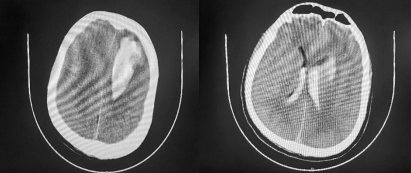

术前CT

经脑科医院神经外科二病区纪文军主任查阅CT影像后,指出苏先生脑出血并非常见部位,结合既往无基础疾病,判断脑出血极有可能是脑动静脉畸形所致,需立即进行全脑血管造影术,如发现脑动静脉畸形可同时处理病灶。